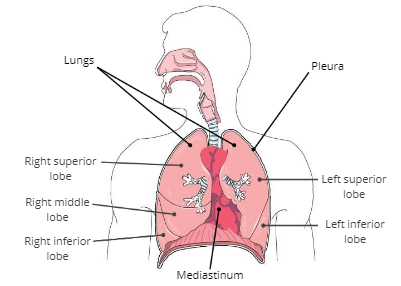

Lungs

soft, spongy organs in the thoracic cavity that are responsible for gas exchange

Mediastinum

a compartment in the center of the thoracic cavity that contains the heart, trachea, and esophagus.

Pleura

a thin, double membrane that surrounds each lung and lines inner surfaces of the thoracic cavity

Pleural fluid

fluid in between the pleura that reduces friction during breathing